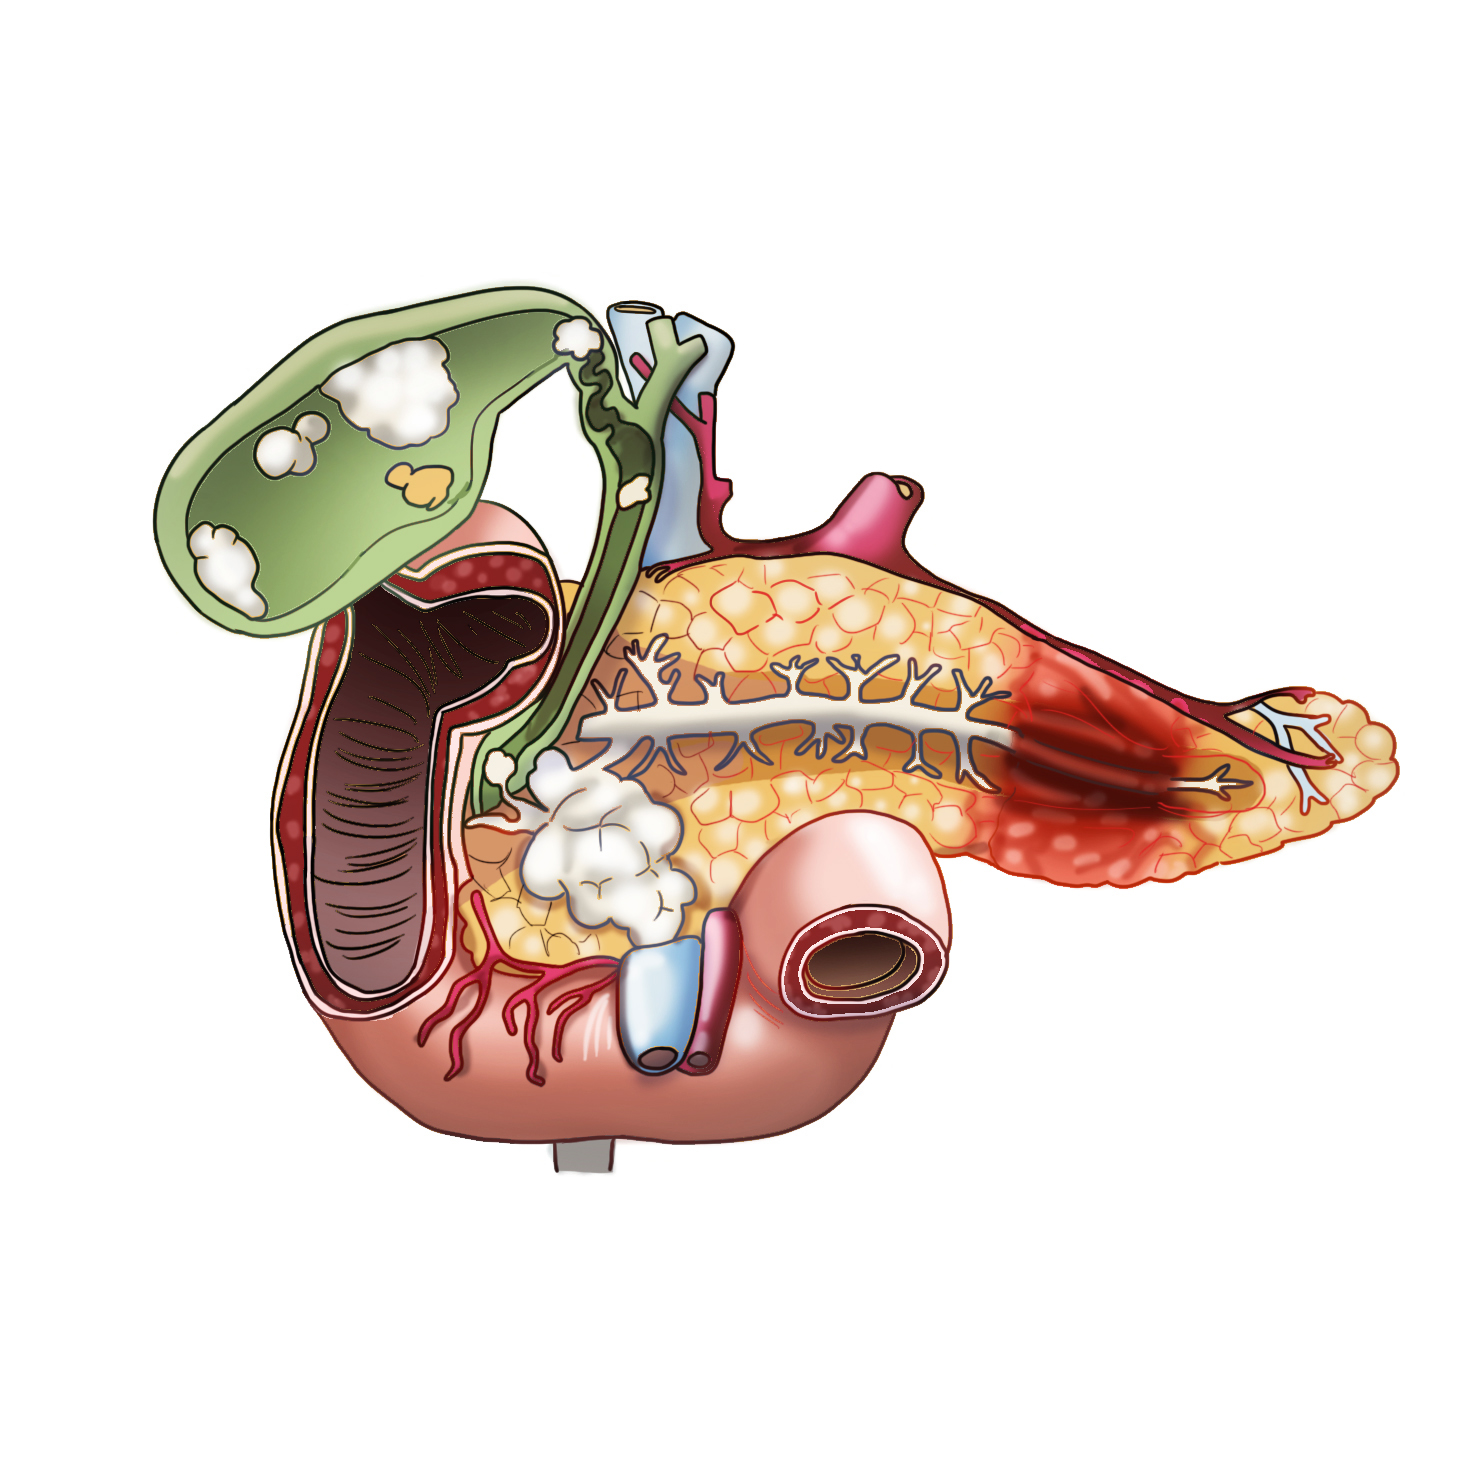

황달은 췌장 머리에 생긴 종양이 소장으로 이어지는 총담관 부분을 막아 담즙의 흐름을 막고 혈중 빌리루빈 수치를 상승시킬 때 발생하는데, 췌장 머리에 생긴 암의 약 80%에서 발생합니다. 몸통이나 꼬리에 생긴 종양의 5~6%만이 황달을 유발하며, 황달이 발생할 때는 이미 암세포가 췌장 전체에 퍼져 간이나 림프절로 전이된 경우가 대부분입니다. 혈중 빌리루빈 수치가 증가하여 황달이 발생하면 피부와 눈 흰자위가 노랗게 변하고 소변 색이 갈색으로 변하며 대변 색이 회백색으로 변하고 피부가 가렵습니다.

평소보다 적은 양의 음식을 먹었는데도 지나치게 포만감을 느낄 수 있는데, 이는 췌장에 생긴 종양이 담관을 막아 공급되어야 할 담즙이 간과 담낭에 축적되기 때문입니다. 간과 담낭에 쌓인 담즙은 간과 담낭을 비대하게 만들어 장기에 압력을 가하고 평소와 다른 포만감을 준다고 합니다.